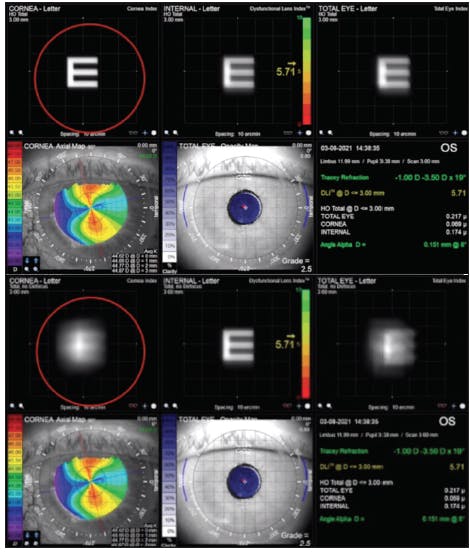

Toric monofocal IOLs. A lens technology that I feel has potential for greater use in patients with glaucoma are toric monofocals. Patients with astigmatism, especially higher amounts, lose contrast sensitivity with spectacle-based versus lens-based astigmatism correction. Therefore, I educate patients on why they are likely to achieve better visual outcomes with a monofocal IOL with built-in astigmatism correction, and I find the iTrace (Tracey Technologies) to be a valuable tool for this purpose. Using this device, I can show patients what their quality of vision would be like with and without astigmatism correction (Figure 1). This information has helped me appreciate how lower amounts of astigmatism still negatively affect quality of vision. It also helps me verify whether patients with lower magnitudes of astigmatism will benefit from astigmatic correction and enables me to confidently offer a toric IOL if so. Now, with lower-power toric IOLs such as the enVista toric (Bausch + Lomb), I often correct corneal astigmatism down to 0.75 D, especially when it is against the rule.

Figure 1. Toric IOL candidates can see their potential vision with (top) and without (bottom) astigmatism correction.